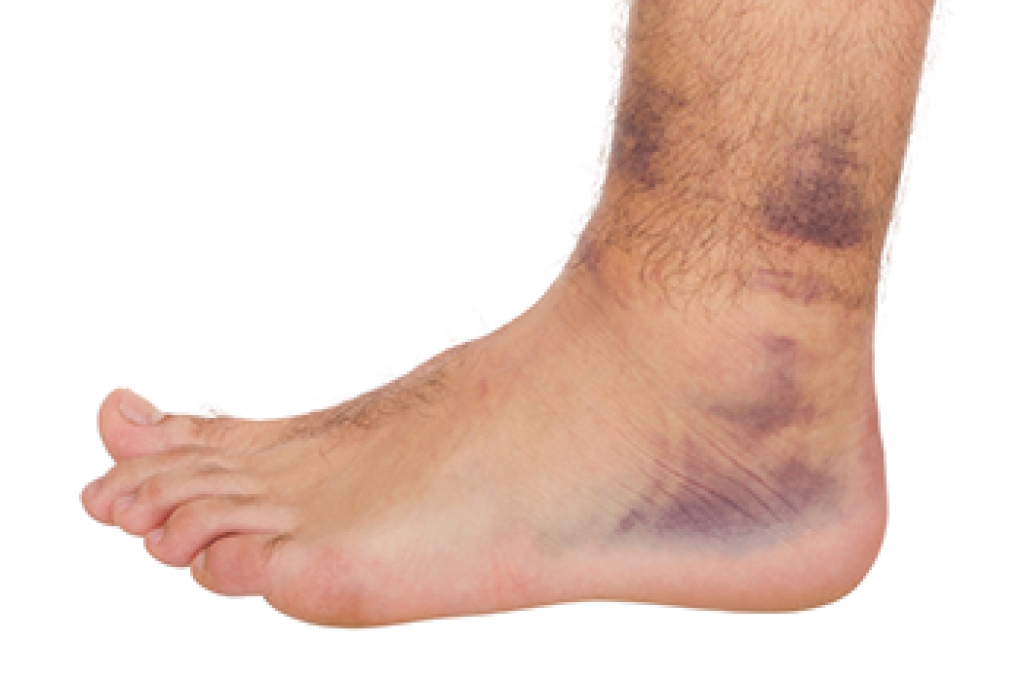

A Podiatrist’s Role in Relieving Ankle Pain

Ankle pain is discomfort that affects the joint connecting the foot and lower leg, an area that supports movement of the toes and calves while allowing stability during daily activities. Symptoms can include swelling, tenderness, changes in gait, deformity of the ankle, difficulty moving the ankle or toes, and an inability to bear weight. These issues may come from injury, arthritis, or structural problems. A podiatrist can evaluate the joint, provide a precise diagnosis, offer treatments that improve mobility, reduce pain, and prevent further injury. If you have ankle pain, it is suggested that you seek expert podiatric care to restore comfort and function, beginning your path to relief.

Ankle pain is any condition that causes pain in the ankle. Due to the fact that the ankle consists of tendons, muscles, bones, and ligaments, ankle pain can come from a number of different conditions.

The most common causes of ankle pain include:

- Types of arthritis (rheumatoid, osteoarthritis, and gout)

- Ankle sprains

- Broken ankles

- Achilles tendonitis

- Achilles tendon rupture

- Stress fractures

- Bursitis

- Tarsal tunnel syndrome

- Plantar fasciitis

Symptoms

Symptoms of ankle injury vary based upon the condition. Pain may include general pain and discomfort, swelling, aching, redness, bruising, burning or stabbing sensations, and/or loss of sensation.

Diagnosis

Due to the wide variety of potential causes of ankle pain, podiatrists will utilize a number of different methods to properly diagnose ankle pain. This can include asking for personal and family medical histories and of any recent injuries. Further diagnosis may include sensation tests, a physical examination, and potentially x-rays or other imaging tests.

Treatment

Just as the range of causes varies widely, so do treatments. Some more common treatments are rest, ice packs, keeping pressure off the foot, orthotics and braces, medication for inflammation and pain, and surgery.